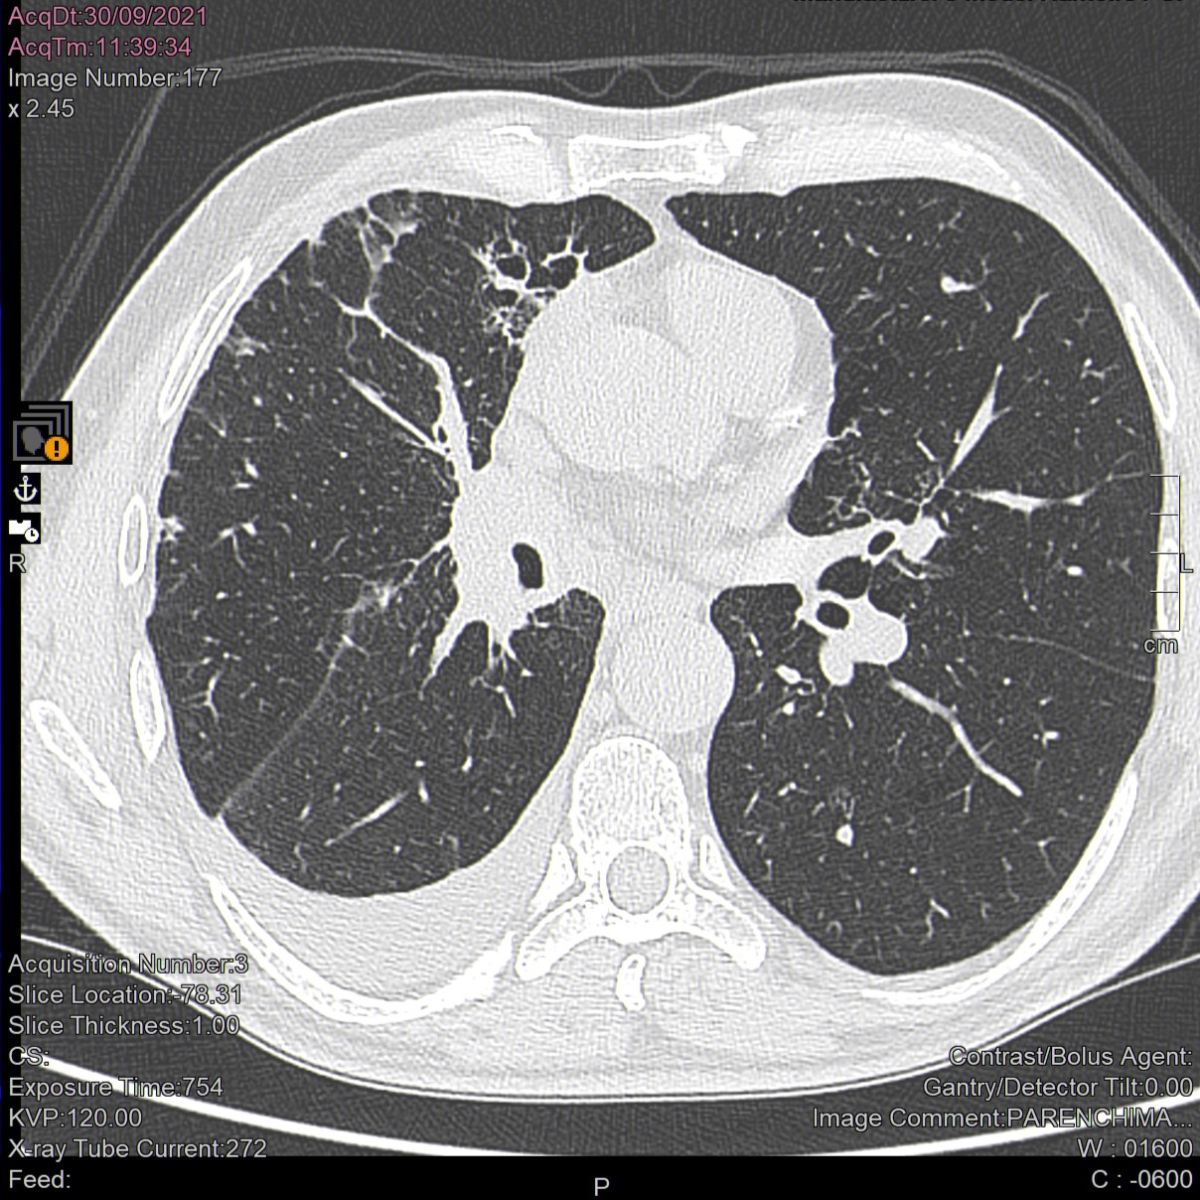

The patient started first-line immunotherapy with pembrolizumab (Keytruda®) 200 mg every three weeks on June 21, 2021. After the fourth pembrolizumab dose (800 mg cumulative dose), the patient had an optimal antitumour response (figures 1 and 2) but developed hypothyroidism (thyroid-stimulating hormone levels 30.04 mIU/l; normal values [n.v.] 0.5–5.0 mIU/l). Replacement therapy with levothyroxine 75 mcg per day was prescribed. Concurrently, the patient reported upper limb myalgia and muscle weakness, exacerbation of his chronic eczema with new areas of skin involvement, and moderate dyspnoea on exertion.

Figure 2Computed tomography scan of the lungs after 3 months of treatment with pembrolizumab. A considerable reduction in the size of the hilar tissue is apparent 3 months after pembrolizumab initiation. The middle lobe has re-expanded and the apical segmental bronchus of the lower lobe is newly patent. Parenchymal localizations have disappeared from the lower lobe and upper lobe lymphangitis has lessened.